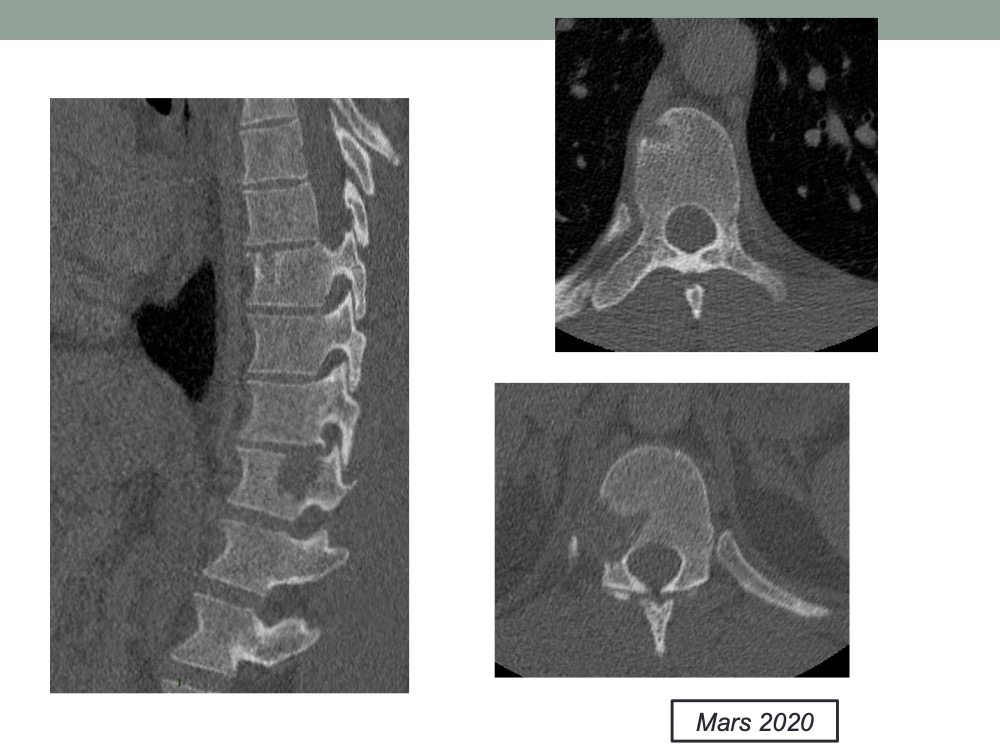

Une lombalgie pas si commune

Augustin Gaudemer 22/06/2020